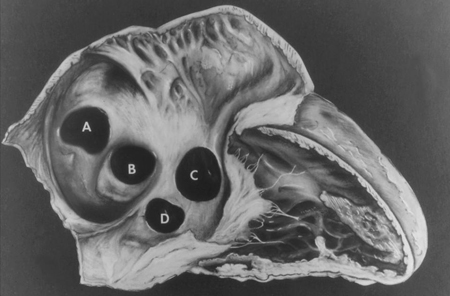

Subtipos dos defeitos do septo ventricular: (A) saída; (B) perimembranoso; (c) entrada; (D) muscular

Mayo Clinic Foundation